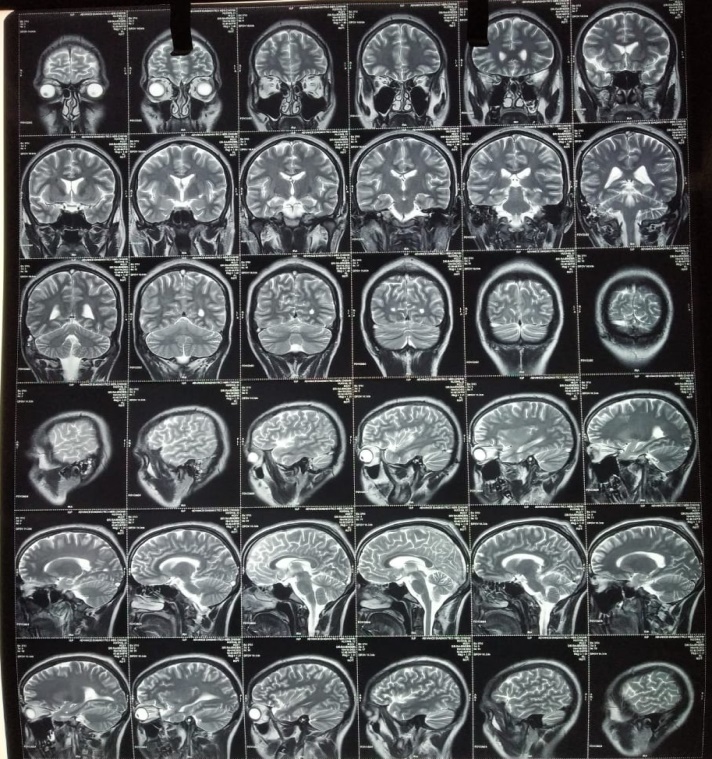

A twenty-two-year-old male, admitted to the medicine ward with a history of headache, binocular double vision, and vomiting, was sent to the department of ophthalmology for fundus examination. His general physical examination, systemic examination, routine blood investigations, and neuroimaging were within normal limits as per records. There was no previous history of any systemic disease. Fundus examination revealed bilateral papilledema (Figures 1a and 1b). A suspicion of hypoparathyroidism was also kept as it is often an important, but an overlooked condition. So before performing any further laboratory investigations, the medical specialist ordered an ultrasonography of the neck which revealed right internal jugular vein thrombosis. His serum calcium levels were within normal limits. A repeat magnetic resonance imaging plus magnetic resonance venography of the brain and orbit revealed ' absent flow related enhancement in superior sagittal sinus, right transverse sinus, right sigmoid sinus and right internal jugular vein suggestive of venous sinus thrombosis plus findings suggestive of mastoiditis (right) were also found (Figure 2). His definitive treatment was started by the medical specialist along with workup for coagulation profile, plus an ENT consultation.

Figure 2: The MRI collage of brain and orbit.